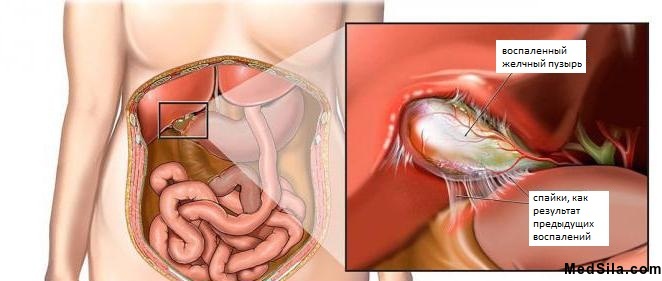

Воспаление в стенках органа ведут к определенным изменениям его структуры: стенки утолщаются и деформируются, слизистая утончается и принимает форму сетки, мышечная оболочка увеличивается, появляются рубцы. При переходе воспаления в более глубокие слои могут образовываться спайки с соседними органами.